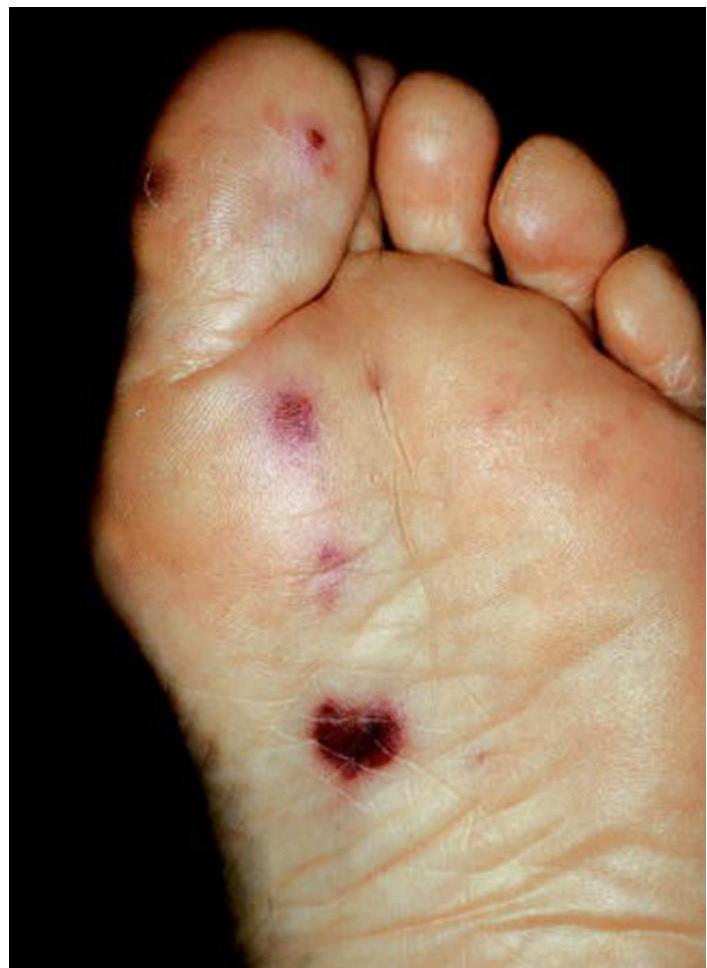

Infective Endocarditis

Signs:

- Janeway lesions: Painless, hemorrhagic, flat plaques on palms and soles (septic emboli)

- Osler’s nodes: Painful, reddish, raised nodules on finger pads/toes (immune complex deposits)

Cause:

- Streptococcus viridans

Management:

- Penicillin and gentamicin

Investigation:

- Echocardiogram